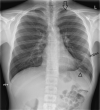

Non-traumatic complications of a solitary rib osteochondroma; an unusual cause of hemoptysis and pneumothorax

Osteochondromas are a very common and usually asymptomatic entity which may originate anywhere in the appendicular and axial skeleton. However, the ribs are a rare site of origin and here they may prove symptomatic for mechanical reasons. In this case report, we describe an unusual case of a symptomatic osteochondroma of the rib secondary to its location and unique shape, ultimately requiring surgical intervention.